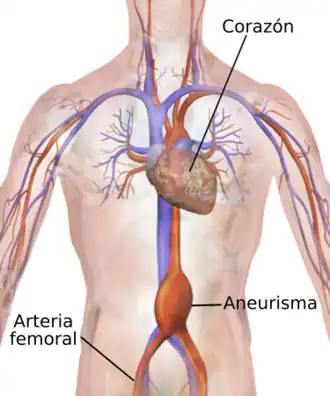

- Aneurisma de aorta. Es una dilatación localizada en un sector de la pared de la arteria.[13]

- Coartación aórtica. Consiste en un estrechamiento localizado de la arteria.

- Disección aórtica. Es un desgarro de la pared arterial que permite que la sangre fluya entre sus capas y las fuerce a separarse, formando una falsa luz en la pared.[13]

- Rotura traumática. Puede ser por herida o traumatismo grave, por ejemplo atropello y aplastamiento del tórax. Es una situación muy grave con alta mortalidad.

- Transposición de los grandes vasos. Es una enfermedad congénita en que la arteria aorta sale del ventrículo derecho en lugar del ventrículo izquierdo.

- Ateroesclerosis. Consiste en el depósito de sustancias lipídicas en la capa íntima de la pared arterial.

- Úlcera aórtica penetrante. Consiste en la formación de una ulceración sobre una lesión previa por arterioesclerosis, penetrando en la pared a cierta profundidad.[13]

- Síndrome aórtico agudo. No es una enfermedad en sí misma, puede deberse a úlcera penetrante, hematoma intramural o disección aórtica. Los síntomas se inician de forma aguda, destacando el dolor torácico.